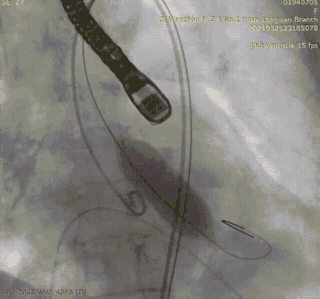

患者主动脉弓部走行角度较大,心腔较小,不利于输送系统跨瓣。术者团队根据术前拟定的策略,改用Snare圈套器,顺利完成跨瓣,将瓣膜送至工作区域。释放前1/3段行造影,确定瓣膜位置。选择窦底上方2mm位置的高位进行释放。

Snare辅助输送系统跨瓣